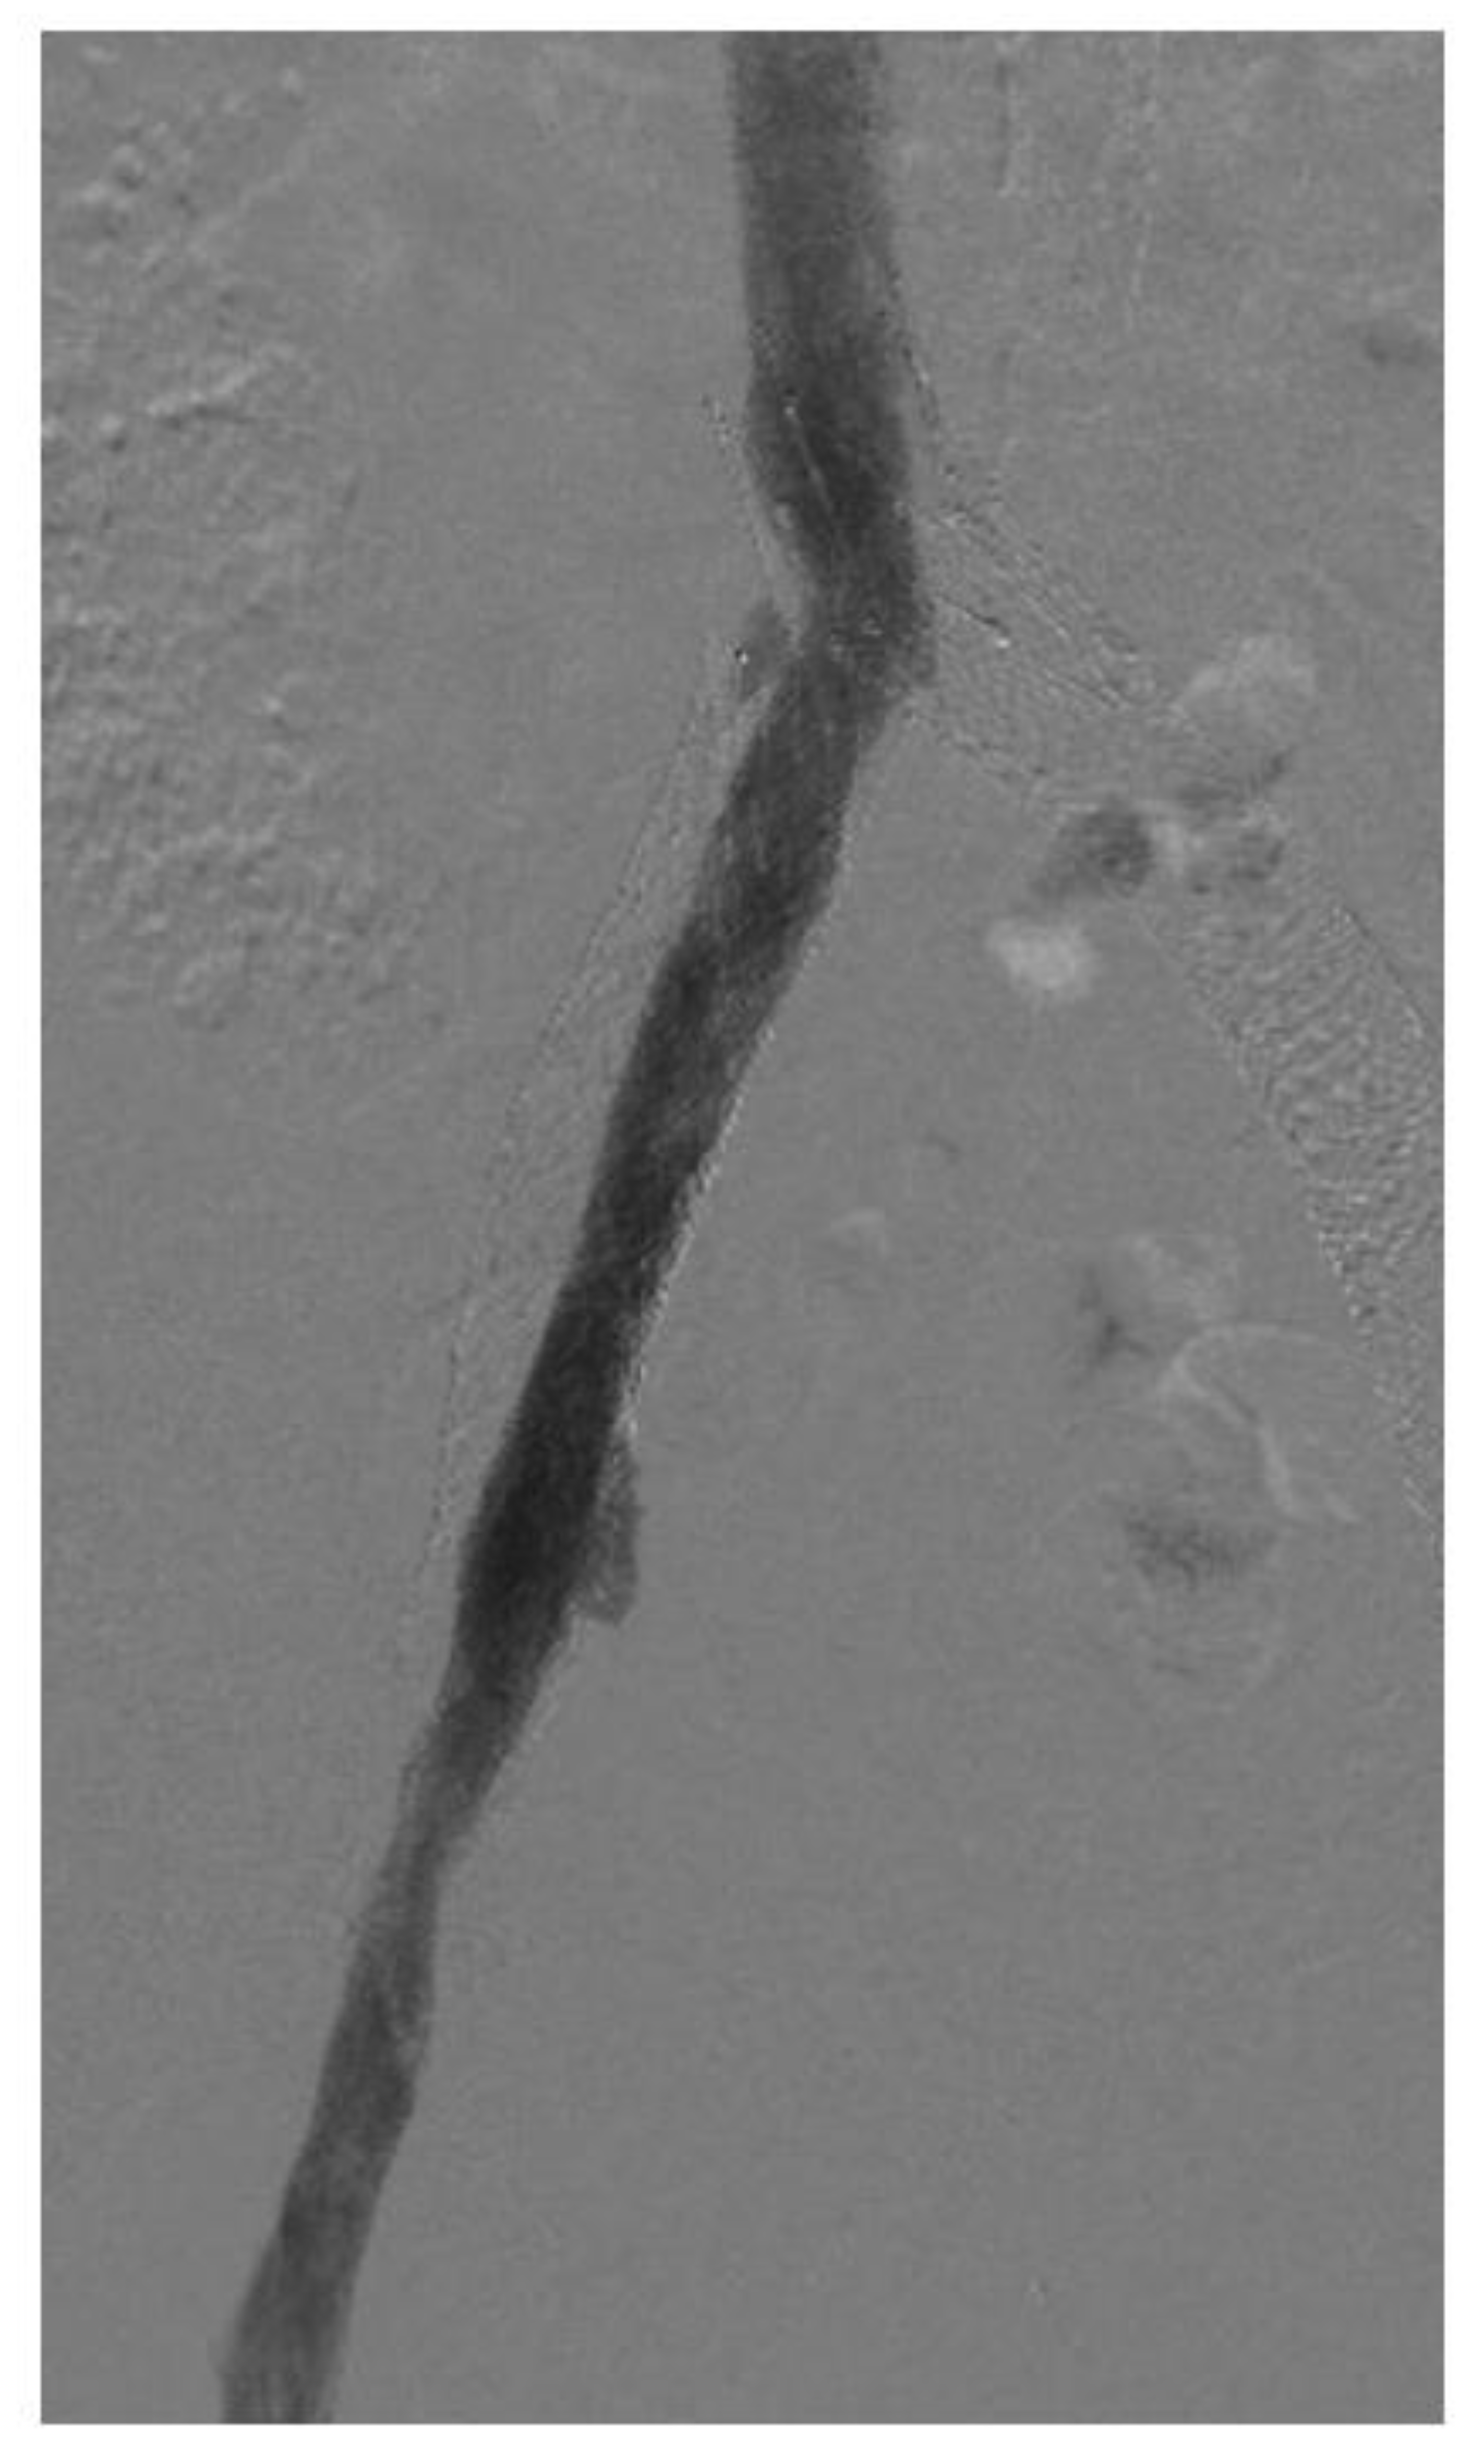

Figure 3.

Venogram showing in-stent restenosis in the stent (about 50%). Notice that the contrast does not completely fill the stent lumen.

In-stent restenosis (ISR) causes stent malfunction that can be unavoidable in certain cases (Figure 3). There are two important considerations with respect to ISR in patients with venous stents. Firstly, about 20–40% ISR is common in most venous stents. Secondly, ISR very rarely leads to complete stent occlusion (<10%). This in turn has led to two modifications in stenting techniques: firstly, slightly oversizing of Wallstents is recommended so that it can somewhat compensate for future development of ISR while also allowing for more aggressive balloon dilatation. Secondly, there is no role or recommendation for the prophylactic balloon dilatation of stents with ISR in asymptomatic individuals. ISR is affected by two main factors: a stent inflow area <125 mm2 and shear rate >100 s−1. Tapered stent profile may help with the latter. Drug eluting balloons and stents also represent a future area of research in the prevention of ISR in the iliofemoral venous system but the large surface area involved compared to arterial or coronary systems must be carefully considered [32,33].